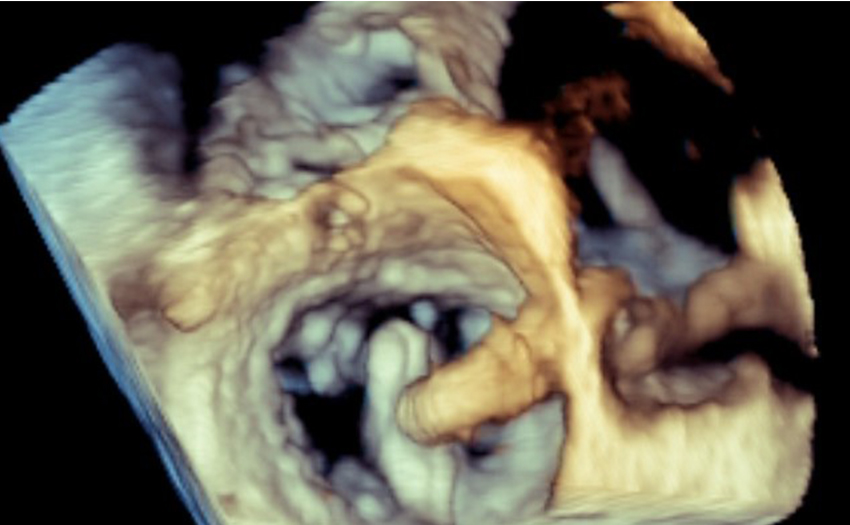

- Advanced Echocardiography: State of the art training on 3D TTE/TEE, Strain, Structural/Interventional Echocardiography. Participation in the latest clinical trials and latest structural interventions. Unparalleled interventional echo experience: (600 TAVR per year, 100 mitral interventions per year, 300 left atrial appendage occlusions per year, 50 tricuspid interventions per year).